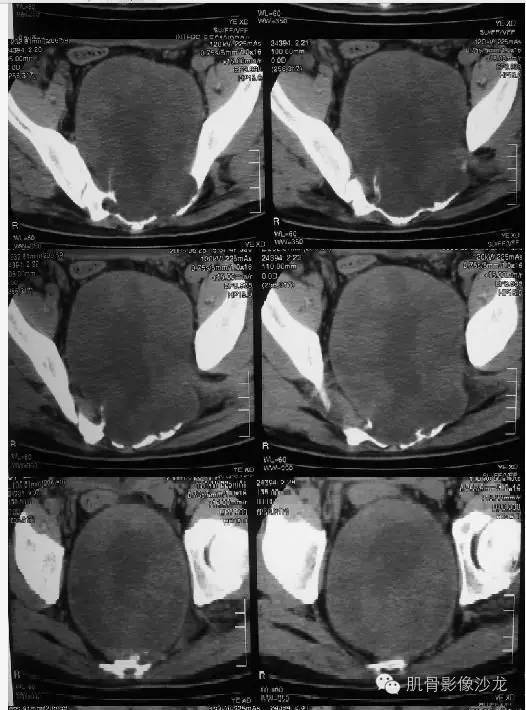

【病例】骶骨神经纤维瘤一例CT影像表现

首先定位,骶尾部骨质破坏,局部巨大软组织肿块,来源于骨?还是软组织病变?

从轴位像上看,病变起源于骶管内可能性大

明显膨胀,偏心,累及骶管骶孔

密度不均,有大范围低密度区

软组织范围大于骨质破坏,向盆腔方向生长远远大于向背侧,所以考虑软织来源

骶孔扩大,哑铃样生长,密度不均匀,强化不均匀强化

骶骨成受压改变

病史:32岁,男性,大小便困难2年,加重伴左侧腰骶部疼痛2个月。

病理:骶骨神经纤维瘤,细胞生长活跃伴局部细胞异型性。